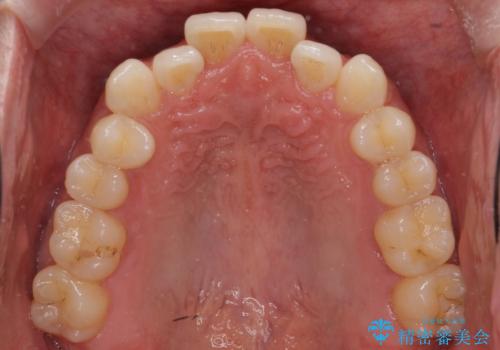

- 受け口を主訴に来院。

前歯の反対咬合でしたが、かみ合わせが、下顎が大きく前方にずれていました。

引っ込んでいる前歯の前方に下の犬歯が深く咬み込んでおり、また、奥歯のかみ合わせも受け口方向にずれ、骨格性の反対咬合も少々ありました。

上の前歯を前方に出すだけでは治療ができないため、ミニスクリューを用いて下の奥歯を後ろに送っています。

また、下の前歯を0.3mmずつIPRしています。